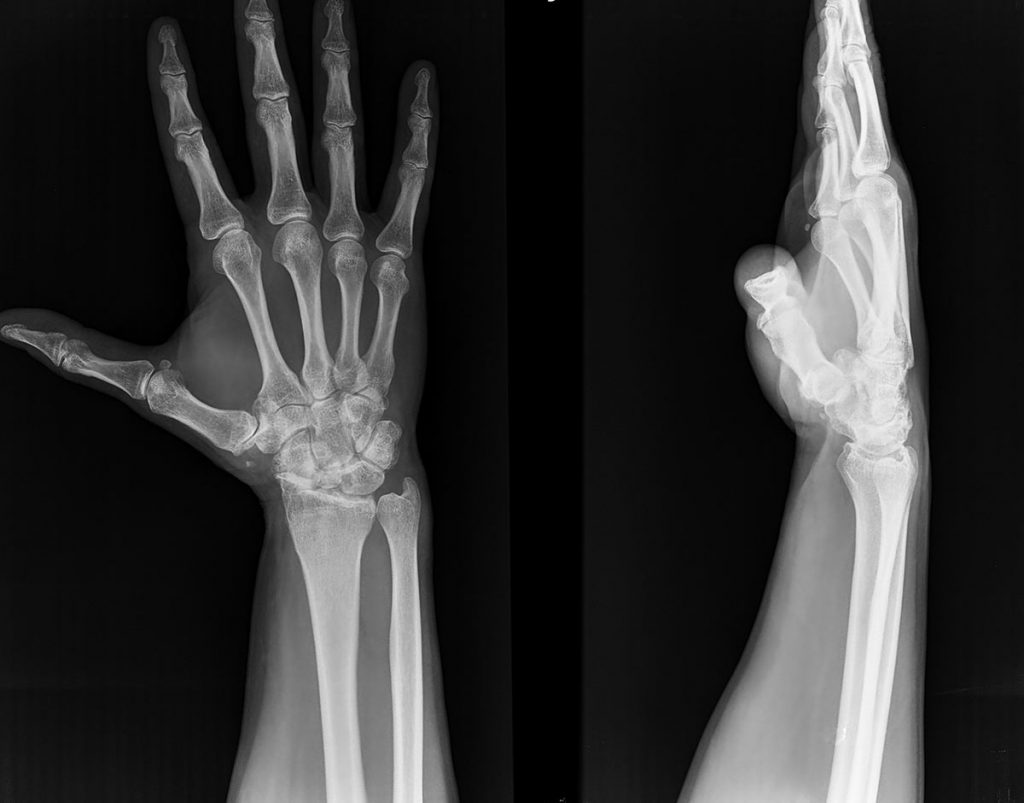

Una «pseudoartrosis» o «no unión» del escafoides consiste en una fractura del hueso escafoides que NO ha consolidado. (Figura 1)

PATOLOGIAS MUÑECA - PSEUDOARTROSIS DE ESCAFOIDES Figura 1 - Pseudoartrosis de fractura de hueso escafoides

Figura 1 - Pseudoartrosis de fractura de hueso escafoides